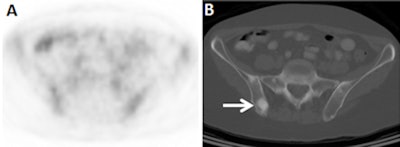

In addition, 10 (11%) of 88 stage III women were upgraded to stage IV; all patients upstaged to IV were confirmed by pathology. Three of the 12 upstaged patients were upstaged based solely on CT images, as their metastases were non-FDG-avid and not detected by PET.

"With ductal breast cancer, distant metastases will be in the bone, liver, and lung, which are more easily seen on FDG-PET," he said. "Lobular breast cancer will more often give metastases to the gastrointestinal tract and the peritoneum, which are more difficult to analyze on FDG-PET and may be better evaluated by CT."